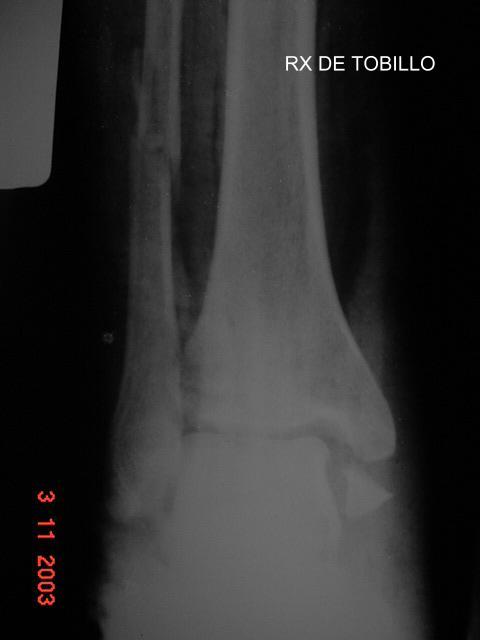

fRACTURA MULTIPLE DE TOBILLO

Las tres Rx son del mismo paciente. UNA RADIOGRAFÍA de pierna que cataloga al paciente como fractura del peroné solamente. La clínica se impone. Las otras radiografías confirman a la clínica.